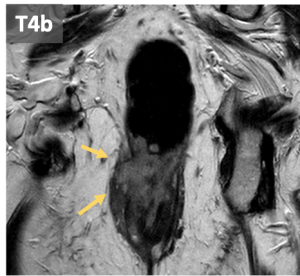

- T4: can be classified in:

- T4b: invasion or pelvic organs including: pelvic organs, vascular structures outside the mesorectum, fat outside the mesorectum, small or large bowel in the pelvis, excretory system (ureters and urethra), muscle (external anal sphincter, puborectalis, levator ani, obturator, piriformis and ischioccygeus), sciatic or sacral nerves, ligaments (sacrosìnous /sacrotuberous), bone.